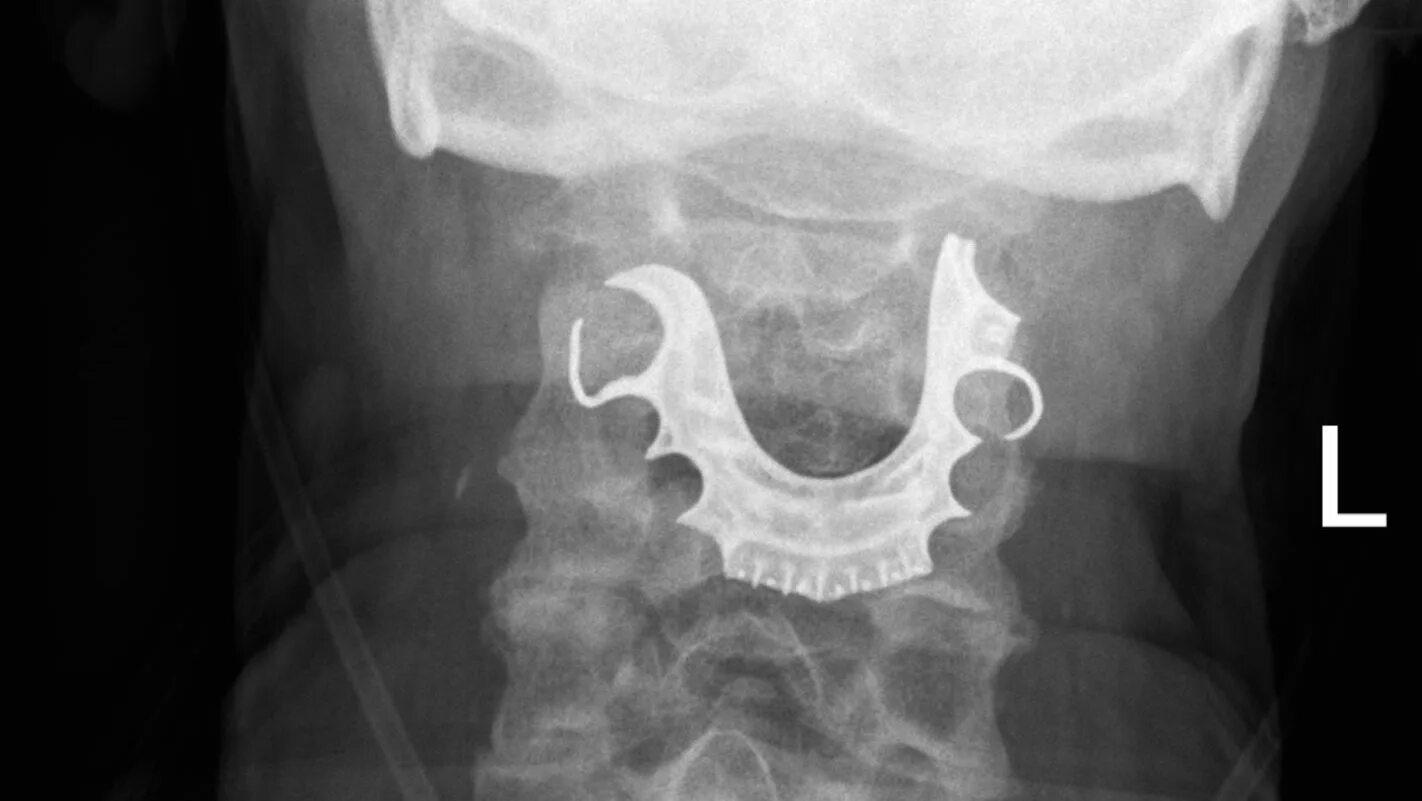

Как достать косточку из горла